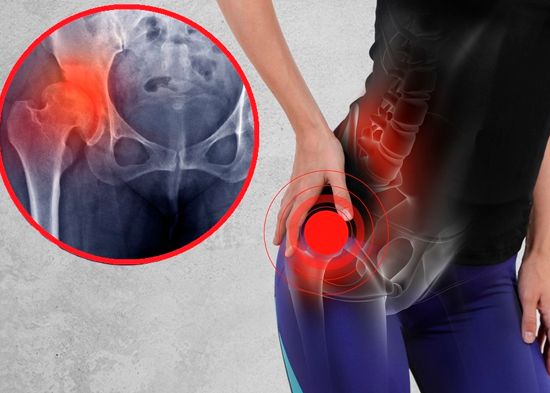

Los síntomas más comunes son: la aparición de aftas, llagas, ampollas dolorosas que se forman en la boca cuando la infección está activa, es posible contraerla si al besar tienes una herida abierta, por sexo oral, anal o genital.

La HSV 2 se refiere al herpes genital que se tramite mediante el sexo oral, anal o genital, pero también se puede contraer al besar a alguien que lo padece a diferencia de la primera, las llagas dolorosas se desarrollan más en los genitales.